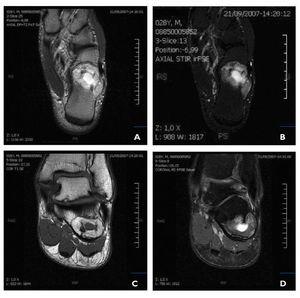

El estudio radiológico se completa con la realización de resonancia magnética (RM) utilizando planos sagitales, axiales y coronales en T1, T2 y en short time inversion recovery (STIR) (fig. 2). La imagen STIR resulta muy útil en este caso, ya que suprime la señal del tejido adiposo normal.

Figura 2 Imágenes de RM en corte axial T2 (A), corte axial STIR (B), corte coronal T1 (C) y corte coronal T2 fat sat (D). Lesión de señal mixta en el cuello-cuerpo del calcáneo de bordes circunscritos de 33,4 x 3,5 x 2 cm en la que se observan áreas de señal adiposa entremezcladas con áreas de calcificación u osificación de apariencia trabecular con ausencia de señal. Asimismo se observa la presencia de una zona central de apariencia quística.